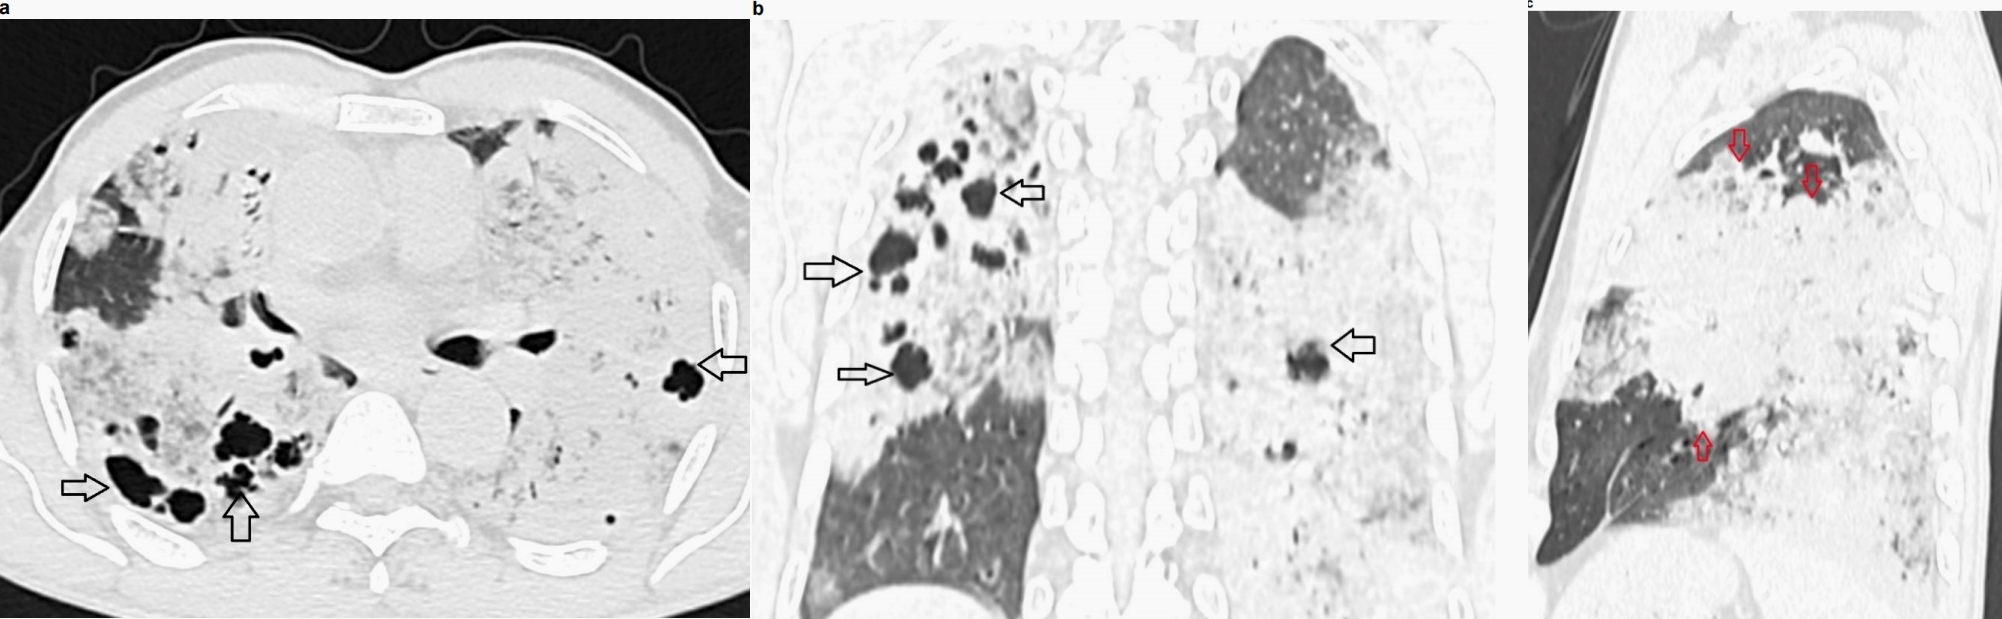

显示双肺广泛实变,其间有磨玻璃影、间隔增厚及多发小囊性/空洞区。部分实变显示内部低密度区(衰减值范围为15-25 HU)。无胸腔积液

或明显的纵隔淋巴结肿大。

图2 胸部非增强CT,肺窗显示双侧肺广泛实变,伴多发囊性区,提示假性空洞(图2a和2b中的黑色箭头),叶间裂膨隆征(图2c中的红色箭头)。